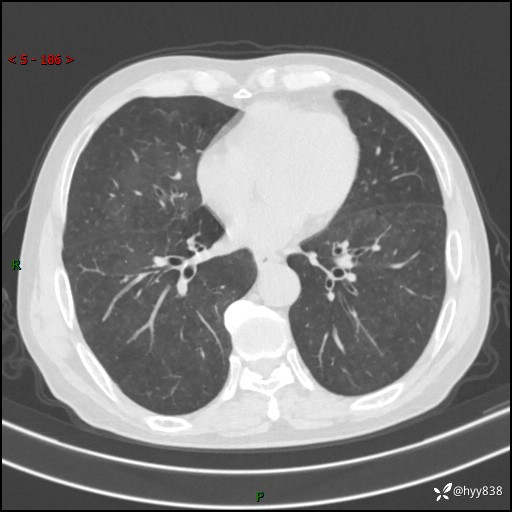

辅助检查:CT

胸部CT平扫